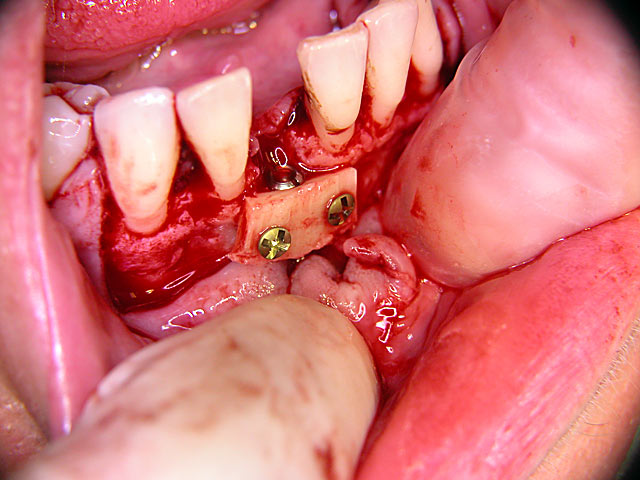

Implantation mit Knochenblock-Implantaten: